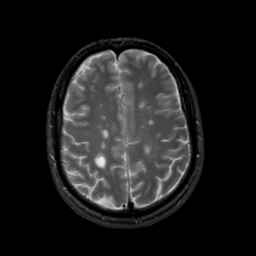

MR Study #2, February 17, 1991 -- Slice #36

[Home][Help][Clinical][Tour 1][Tour 2] Slice 36